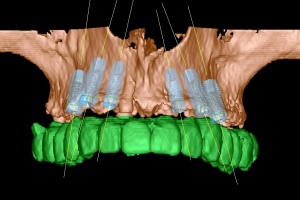

Im Oberkiefer konnten mit der Planungssoftware SkyPlanX der Firma Bredent 6 Implantate mit BoneSplit geplant werden (Abb. 2), im Unterkiefer war eine Implantation aufgrund ungenügenden Knochenangebots nicht möglich.